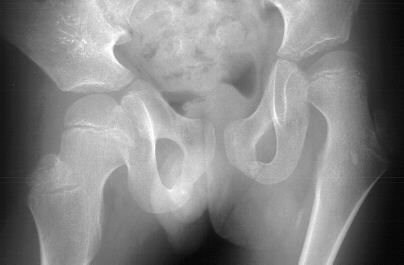

XRAYS:

Radiographic findings of HO on plain films is evident at 4-6 weeks, usually trabeculation is absent. Payne and DeLuca(10) define HO in soft tissues as radiodensity 5 mm from the femoral shaft and not initially adjacent to the femur which is periosteal callus and HO is usually a flocculent pattern.Technetium three-phase bone scan is positive in the initial phase of HO and is 90% sensitive in 2-4 weeks after injury. Return to baseline is 7-12 months after injury(14). Bone scans may be used to assess the level of maturity of the HO. Computed tomography can differentiate native vs. ectopic bone by revealing the osseous architecture(14).Computed tomography may also be useful in planning surgical approach. Magnetic resonance imaging can demonstrate soft tissue swelling but receives only limited signal from calcified tissue(14). Ultrasound has been shown to detect HO earlier than plain radiographs in eight consecutive patients by Thomas and Amstutz (17).

Classification of HO is well documented by Parkinson et al (22); DeLee(23);and Brooker(24). These classifications were used to describe HO after total hip arthroplasty. A classification developed by Krum and Miller(15) included radiographic and clinical criteria. Grade I was considered when there was no symptoms but radiographic evidence. Grade II was described as having mild-moderate symptoms of pain, irritability, limited range of motion. In grade III lesions hip function was severely limited. The radiographic classification A included those lesions in which the width of heterotopic ossification was less than half of the width of the femoral neck. With B lesions the width of HO was equal to half of the width to the entire width of the iplilateral femoral neck. Grade C heterotopic ossification has lesions greater than width of the ipsilateral femoral neck. Classification of HO about the elbow is described by Hastings and Graham(14). This three part classification focuses on functional limitation with consideration to the anatomic basis of HO distribution.